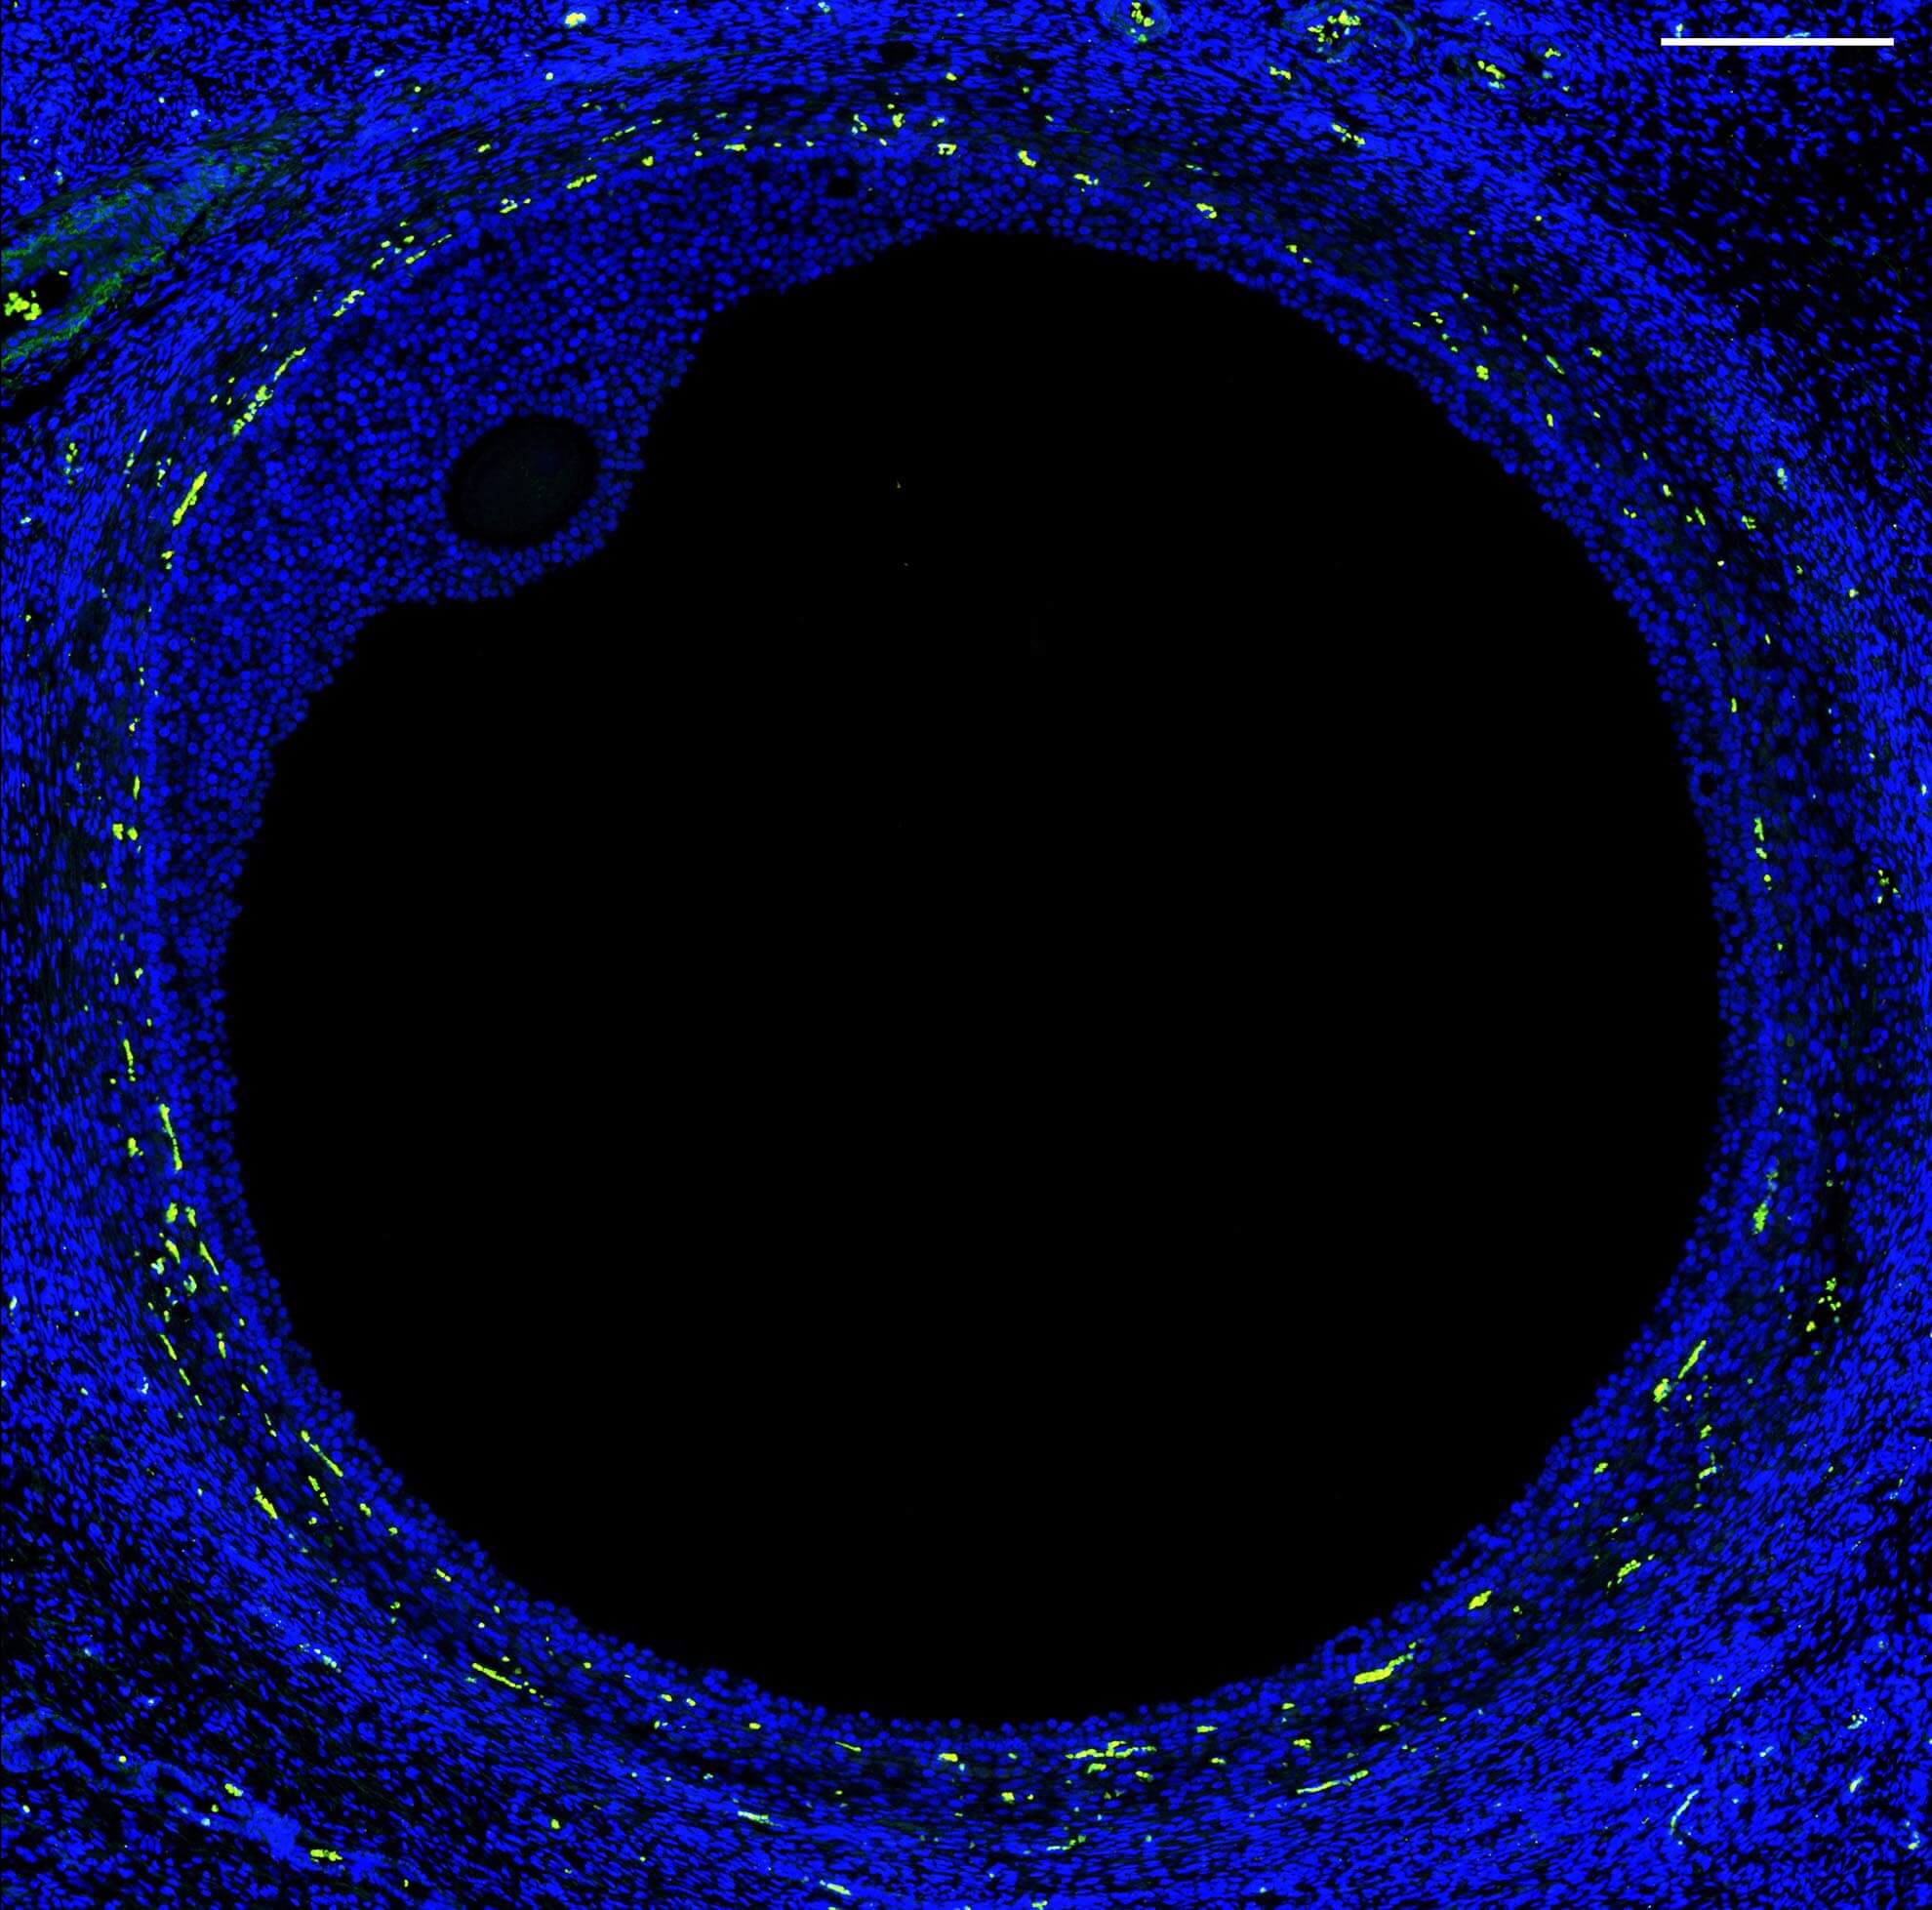

An image from the spatial transcriptomics experiment: a large antral follicle from a human ovary stained with SYTO82 for nuclei (blue), smooth muscle actin (green), and CD68, a macrophage marker (yellow).

A new effort to characterize the fallopian tube is expanding our knowledge of reproductive health and our ability to treat infertility and reproductive diseases. The project is a collaboration between University of Michigan geneticists Sue Hammoud and Jun Li, clinician Erica Marsh and biomedical engineer Ariella Shikanov. They are working toward a human cell atlas of the female reproductive system.

The team used single-cell RNA sequencing to characterize the diversity of cell types in the fallopian tube — the site of fertilization. They identified 12 major cell types in healthy fallopian tissue, including several new types of epithelial cells with finger-like projections that help egg cells travel from the ovary to the uterus. They also found two types of progenitor cells, which can replenish or repair tissue.

“This really is a basecamp to launch future studies,” Jun says.

Future research could focus on understudied conditions such as infertility, endometriosis and ovarian cancer. In fact, initial findings from the fallopian cell atlas suggest the cellular roots of ovarian cancer may be in the fallopian tube. The researchers identified transition cells that could become cancerous under the right conditions.